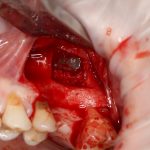

Я зафиксировал костный блок практически без адаптации на несколько винтов. Обрати внимание, что винты находятся в зоне, где не планируется установка имплантатов. Фиксация должна быть надежной, поскольку мне еще предстояла подготовка лунок для имплантатов. Трех винтов для этого вполне достаточно.

Дальнейшая адаптация костного блока свелась к сглаживанию острых краев. После чего я приступил к подготовке лунок и установке имплантатов.